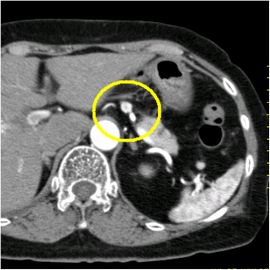

CT検査にて膵体部に腫瘍を認め、精査の結果、膵体部腫瘍疑いと診断し膵体尾部切除術を施行した。

病理診断結果はインスリノーマ(インスリン産生膵島細胞腫)であった。

CT画像